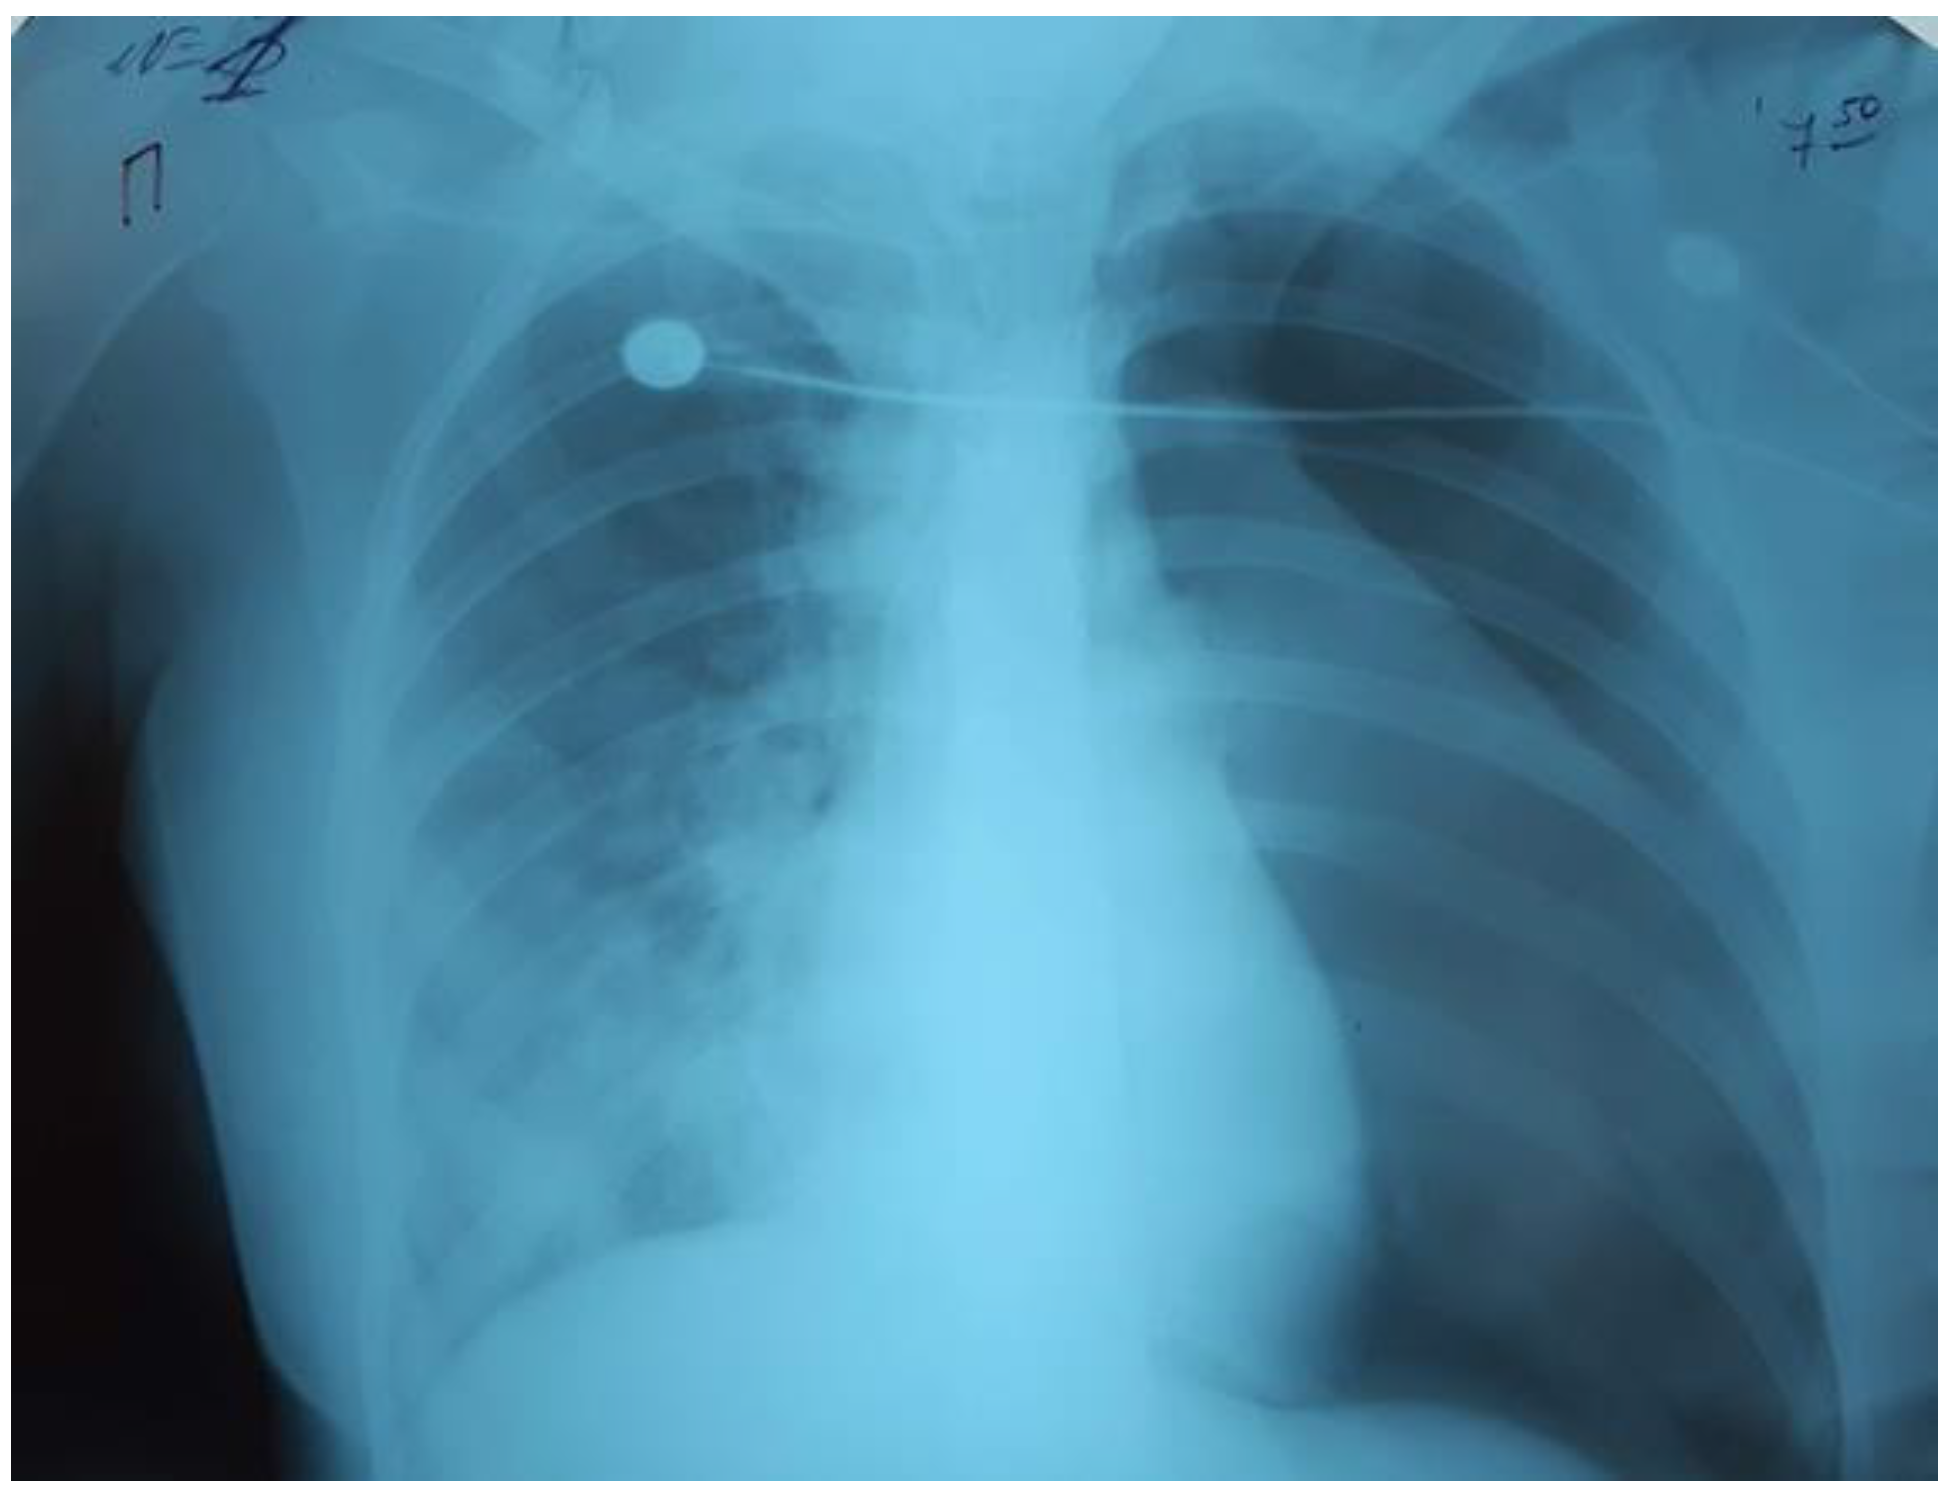

The child’s condition deteriorated within three days. The RF progressed; RR 35/min, SpO286%, oxygen dependence, HR 110/min, BP 100/60 mmHg, the symptom of capillary refill > 3 s, cold extremities. Bilateral polysegmental pneumonia was detected on the chest radiograph (Figure 3). The lung ultrasound showed signs of interstitial syndrome on both sides, alveolar consolidation on the left, left-sided hydrothorax.

Figure 3.

Bilateral polysegmental pneumonia.

On the third day of mechanical ventilation, the girl had a complication—left-sided pneumothorax. The urgent drainage of the pleural cavity (Figure 4) was performed, as well as reduction of mechanical ventilation parameters: P/SIMV, FiO2 80%, PIP 12 cmH2O, PEEP 8 cmH2O, I/E 1-1.5, TV 300 mL/kg.

Figure 4.

Left-sided pneumothorax.